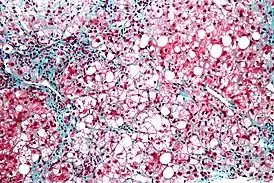

![]() Микрофотография стеатогепатита. Биопсия печени | |